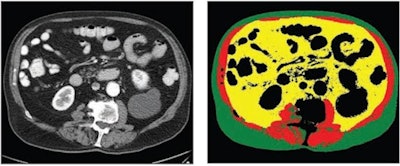

70-year-old white male patient with weight of 79.8 kg, body mass index (BMI) of 29.3, and low cardiovascular risk factors (nonsmoker, no diabetes diagnosis, blood pressure of 120/78). (Left) Axial CT image at level of L3 vertebral body. (Right) Matching automated segmentation label map. Visceral fat area z score is 1.41, corresponding to the 92nd percentile. Patient experienced both subsequent myocardial infarction and stroke. Images and caption courtesy of the American Journal of Roentgenology."[Visceral fat area] from fully automated and normalized analysis of abdominal CT examinations predicts subsequent MI or stroke in Black and White patients, independent of traditional weight metrics, and should be considered as an adjunct to BMI in risk models," the authors wrote.